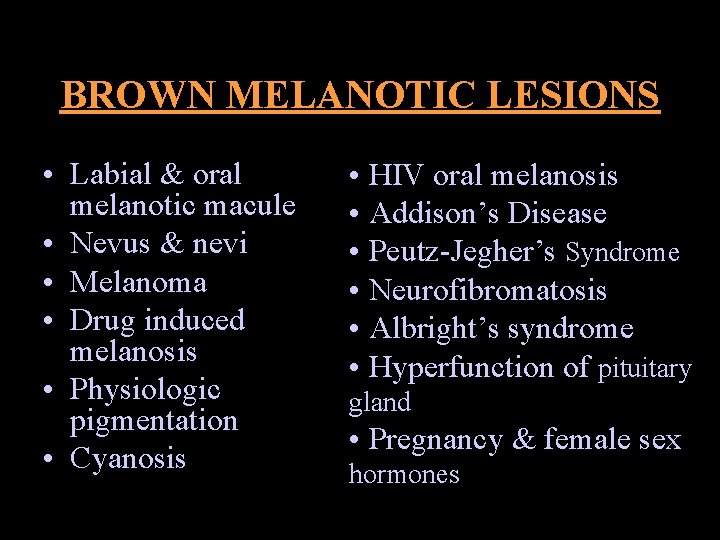

BROWN MELANOTIC LESIONS • Labial & oral melanotic macule • Nevus & nevi • Melanoma • Drug induced melanosis • Physiologic pigmentation • Cyanosis • HIV oral melanosis • Addison’s Disease • Peutz-Jegher’s Syndrome • Neurofibromatosis • Albright’s syndrome • Hyperfunction of pituitary gland • Pregnancy & female sex hormones